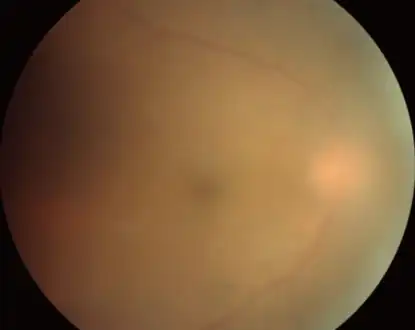

Acute toxoplasmosis is often asymptomatic in healthy adults.[13][14] However, symptoms may manifest and are often influenza-like: swollen lymph nodes, headaches, fever, and fatigue,[15] or muscle aches and pains that last for a month or more. It is rare for a human with a fully functioning immune system to develop severe symptoms following infection. People with weakened immune systems are likely to experience headache, confusion, poor coordination, seizures, lung problems that may resemble tuberculosis or Pneumocystis jiroveci pneumonia (a common opportunistic infection that occurs in people with AIDS), or blurred vision caused by severe inflammation of the retina (ocular toxoplasmosis).[15] Young children and immunocompromised people, such as those with HIV/AIDS, those taking certain types of chemotherapy, or those who have recently received an organ transplant, may develop severe toxoplasmosis. This can cause damage to the brain (encephalitis) or the eyes (necrotizing retinochoroiditis).[16] Infants infected via placental transmission may be born with either of these problems, or with nasal malformations, although these complications are rare in newborns. The toxoplasmic trophozoites causing acute toxoplasmosis are referred to as tachyzoites, and are typically found in bodily fluids.[17][18]

Micrograph of a lymph node showing the characteristic changes of toxoplasmosis (scattered epithelioid histiocytes (pale cells), monocytoid cells (top-center of image), large germinal centers (left of image)) H&E stain